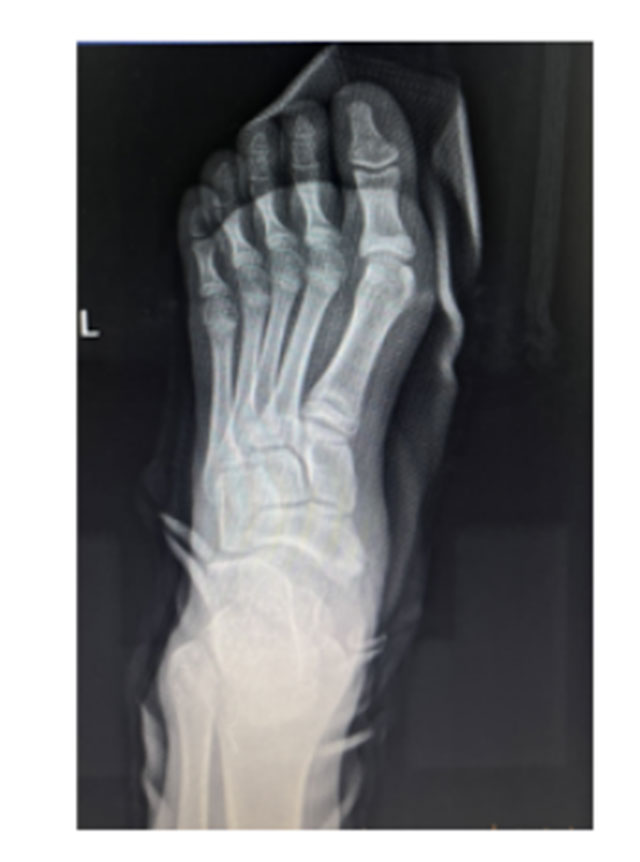

经过专业查体和检查后,张磊博士为其诊断为“左足副舟骨痛综合征”,通俗的说,就是足内侧多长了一块骨头,建议其住院手术治疗。

术前影像学提示左足副舟骨